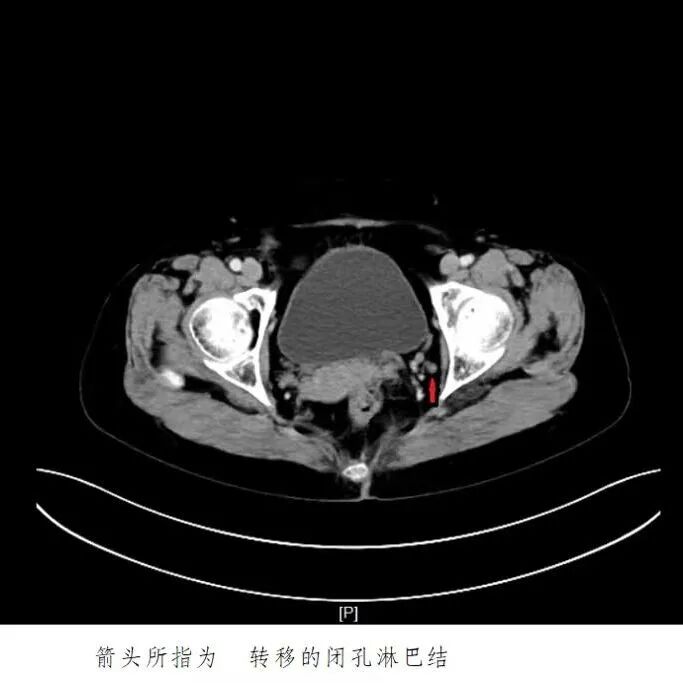

今年劳动节后,郑阿姨排便时总感觉疼痛,偶尔还发现便中带血。起初她没太在意,总想着“也许过几天就好了”。然而症状非但没缓解,反而逐渐加重。5月下旬,她终于来到昆山市中医医院肛肠科就诊。

直肠肿瘤

恶性可能性极大

通过医院内的长三角高级专家会诊服务中心,科室精准对接了上海瑞金医院胃肠外科陆爱国主任。在详细评估郑阿姨的病史与检查资料后,陆主任给出了明确方案:

直肠恶性肿瘤,有手术指征,可行腹腔镜下手术,创伤小、恢复快。